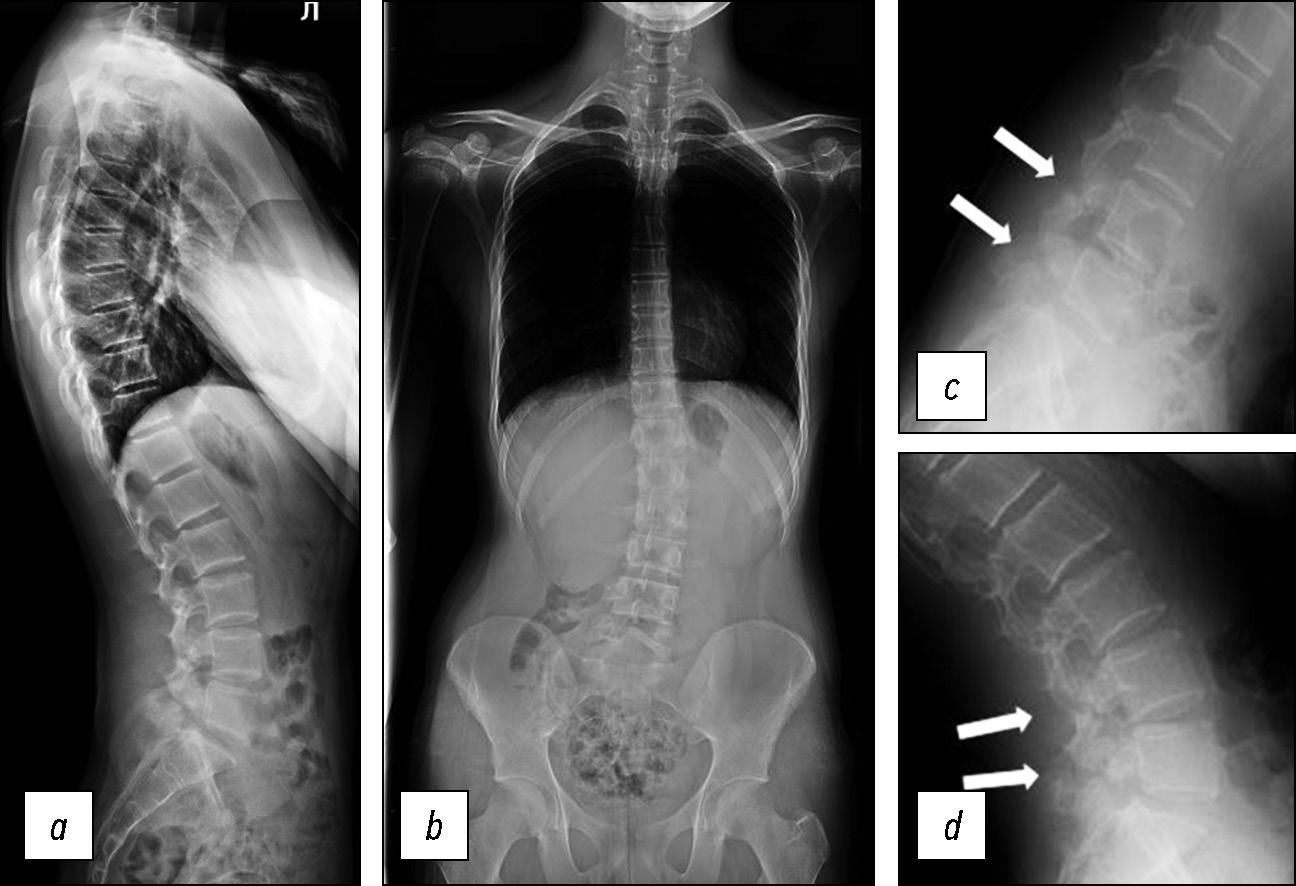

По данным постуральной рентгенографии позвоночника подтверждён диагноз двухуровневого билатерального спондилолиза. Отмечено наличие левосторонней сколиотической деформации поясничного отдела позвоночника с вершиной на уровне L1-L2 позвонков, угол по Коббу — 15°. Параметры сагиттального баланса туловища — без значимых отклонений от нормы (PI=50°, PT=9°, SS=39°, LL=60°, TK=43,6°) (рис. 1а, b). По данным функциональной рентгенографии поясничного отдела позвоночника, в положении сгибания и разгибания в боковой проекции определяется отсутствие явного изменения спондилолизного дефекта дужки L4 позвонка, тень, образованная спондилолизным дефектом на уровне L5 позвонка, при сгибании расширялась (рис. 1c, d).

Рис. 1. Постуральная и функциональная рентгенография позвоночника: a — боковая проекция, b — прямая проекция, c — сгибание, d — разгибание. Стрелками указаны зоны спондилолиза.

Fig. 1. Postural and functional radiography of the spine: a — lateral projection, b — straight projection, c — flexion, d —extension. The arrows indicate the zones of spondylolysis.